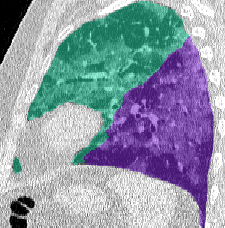

Lung segmentation results for the polymorphic and nonpolymorphic models are shown in Figure 3. Quantitative evaluation of lung segmentations was performed on CT images by comparing the segmentations to ground truth manual segmentations. The Dice coefficient was used to measure volume overlap and the average symmetric surface distance (ASSD) was used to assess boundary accuracy. The ASSD and Dice coefficient results for each of the four evaluation datasets are shown in Table 2. Overall, on the COVID-19 dataset the polymorphic model achieved an average ASSD of mm and average Dice coefficient of . By comparison, the nonpolymorphic model achieved an average ASSD of mm and average Dice coefficient of . ASSD and Dice coefficient results with respect to nonaerated lung volume fraction are displayed in Figure 4. Two-way analysis of variance revealed a significant interaction between model and nonaerated fraction for each evaluation metric, indicating that the regression coefficients with respect to nonaerated fraction were significantly different for polymorphic vs. nonpolymorphic models.

Lobar Segmentation

Lobar segmentation results for the proposed method and PTK are shown in Figure 5 for right lungs and Figure 6 for left lungs. For each image in the COVID-19 dataset (133 images in total), the lobar segmentation result was used to extract the amount of poor aeration () and consolidation () in each lobe. Common phenotypes of COVID-19 affected lungs were identified by hierarchical clustering over the fraction of poorly aerated and consolidated tissue in each lobe. Dendrographic analysis in Figure 7 reveals four primary clusters of patients that were identified by the hierarchical clustering: (a) mild loss of aeration primarily in the two lower lobes without consolidation; (b) moderate loss of aeration focused in the two lower lobes with or without consolidation in lower lobes; (c) severe loss of aeration throughout all lobes with or without consolidation; and (d) severe loss of aeration and consolidation throughout all lobes.